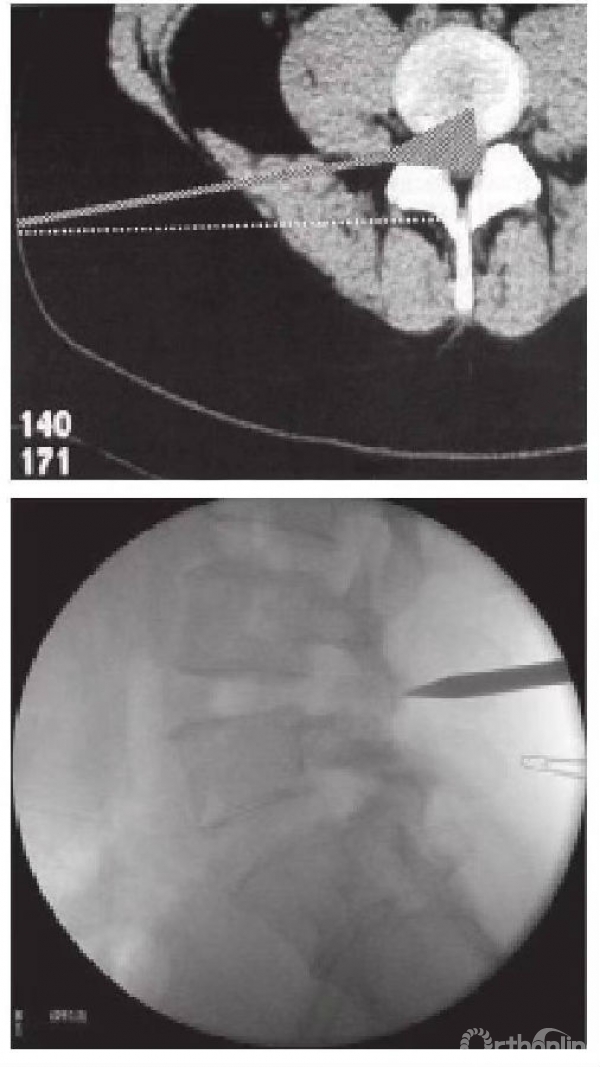

第四个是2004年德国医师Reutten研发的椎板间入路(图6)及侧位导入(图7)两种技术。椎板间入路和我们传统手术的后位入路是一样的,它是由一个斜方的工作导管把神经根或神经管向中央移并推开的技术。椎板间入路通常适用于L5~S1,因为L5~S1有髂后上棘阻挡导管进入方向,所以由后方经椎板间入路有其独到优势。但行此种手术需考虑到突出的椎间盘是在腋下或肩部,先在影像学上(MRI)确认清楚。

图6 椎板间入路

椎间孔入路则涵盖范围非常广,它进入的侧位入口需于小关节的后方(图7),这样才不会整个进入到腹部。因为它涵盖范围非常广,因此可处理几乎所有椎间盘突出,而徐少克大多也选用这样的技术。但是对于高位的椎间盘导入要特别注意,因为高位的椎间盘导入可能会伤到内脏,必须要更靠近后方中线。

图7 椎间孔入路,需从小关节后方导入